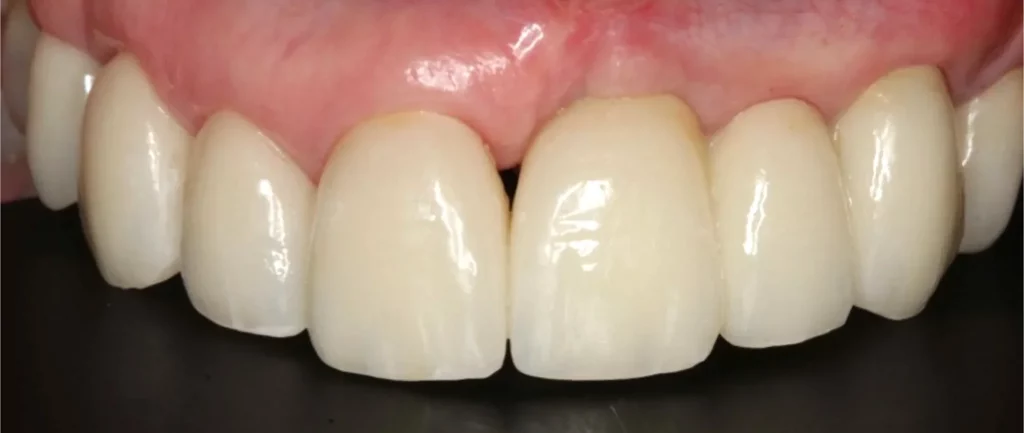

One New Year’s Eve, we received a phone call from a distressed lady who said her top front bridge had fallen out unexpectedly. Regrettably, the two teeth that supported the bridge had decayed and couldn’t be fixed. The patient wanted to avoid wearing a long-term denture and had always longed for a better smile. She was very self-conscious when smiling, and like many people, having her photo taken was not her favourite event.

The above shows the two rotten teeth that were removed and went on to be replaced by two implants with gold posts.

Below is a temporary bridge worn during the treatment phase.

To achieve smile symmetry, the gum was recontoured around the adjacent teeth while others had gum grafts placed to reduce the speed of gum recession. Both the health and appearance of the smile were addressed.